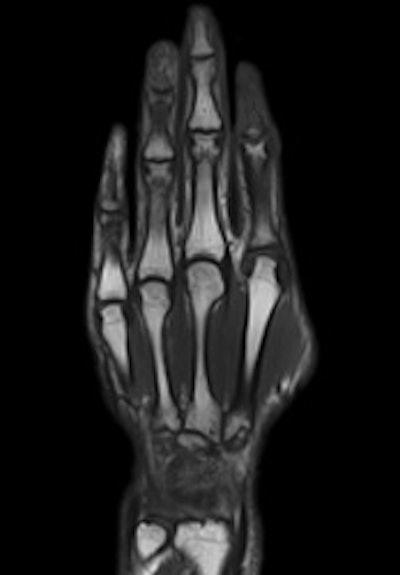

The new scanner features a Siemens' Tim (total imaging matrix) coil and 4G radiofrequency technology for enhanced spatial and temporal resolution. In addition, cableless, direct-connect coils are designed for more efficient setup. As many as 120 coil elements can be combined for larger anatomical coverage and whole-body scans with 205 cm of coverage in a single MRI exam, with no need to reposition a patient or the coils.

"It is a whole-body system fit for all clinical applications, but with an emphasis on broad clinical applications," Ohnesorge said. "Three-tesla MRI truly has proven its clinical differentiation, as in musculoskeletal, spine imaging, and neuroimaging, which in total is 70% to 80% of all MRI examinations. Some of the cutting-edge applications, such as functional MRI, are still subject to more clinical research."